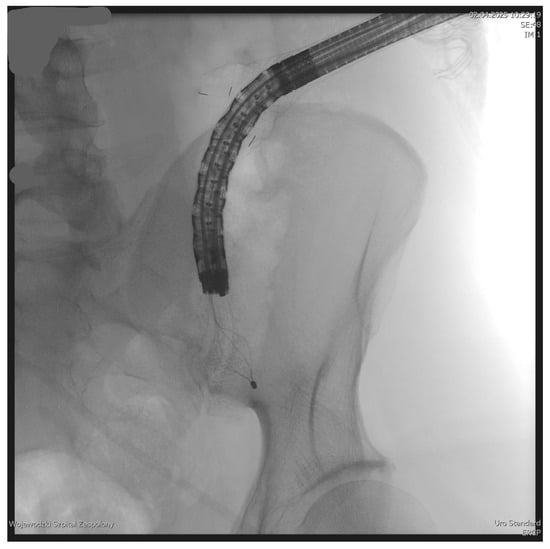

The PEN procedure was performed under general anesthesia with endotracheal intubation in the supine position. Percutaneous endoscopic necrosectomy was performed under the guidance of ultrasound (using a Logiq P9, convex C1-6 MHz probe) and fluoroscopy. Following the establishment of percutaneous drainage, Cook Medical Acrobat 2 AWG2-35-45 guidewire was inserted and looped inside the lumen of the necrotic collection (Figure 1 and Figure 2) to be followed by implantation of a fully coated self-expandable Evolution® esophageal controlled-release stent 120 mm or 150 mm in length and 20 mm in diameter (Figure 3 and Figure 4). A flexible Evis Exera III CF-H190L endoscope–gastroscope (Olympus) was then inserted into the necrotic collection through the lumen of the esophageal stent, and a percutaneous endoscopic necrosectomy procedure involving mechanical removal of necrotic tissue from the collection under direct endoscopic image guidance was performed (Figure 5, Figure 6 and Figure 7). A Dormia basket (Figure 8) was used to remove necrotic tissue. In the course of the percutaneous endoscopic necrosectomy procedure, the necrotic collection was extensively flushed with physiological saline, and the contents from the reservoir were aspirated. The PEN procedure was considered complete upon removal of demarcated necrotic tissues or upon bleeding from the inflammatory granulation tissue within the necrotic collection. If subsequent percutaneous endoscopic necrosectomy procedures were required in the same patient, the esophageal stent was left in the percutaneous position, and one or two 16 Fr silicone drains (depending on the size of the collection) were inserted into the lumen of the necrotic collection through the stent to maintain patency. The drain(s) were used to flush the collection with 100 mL of physiological saline 6 times a day. Following the completion of endoscopic treatment using percutaneous access, the esophageal stent was removed, and the stenting site was secured with a stoma bag to drain the remaining contents from the residual necrotic collection (Figure 9).

Figure 1. Looped guidewire within the lumen of the WOPN cavity. Source: Department of General, Gastroenterological, and Oncological Surgery, L. Rydygier Regional Hospital in Toruń.

Figure 2. Guidewire percutaneously inserted into the lumen of the WOPN collection. Source: Department of General, Gastroenterological, and Oncological Surgery, L. Rydygier Regional Hospital in Toruń.